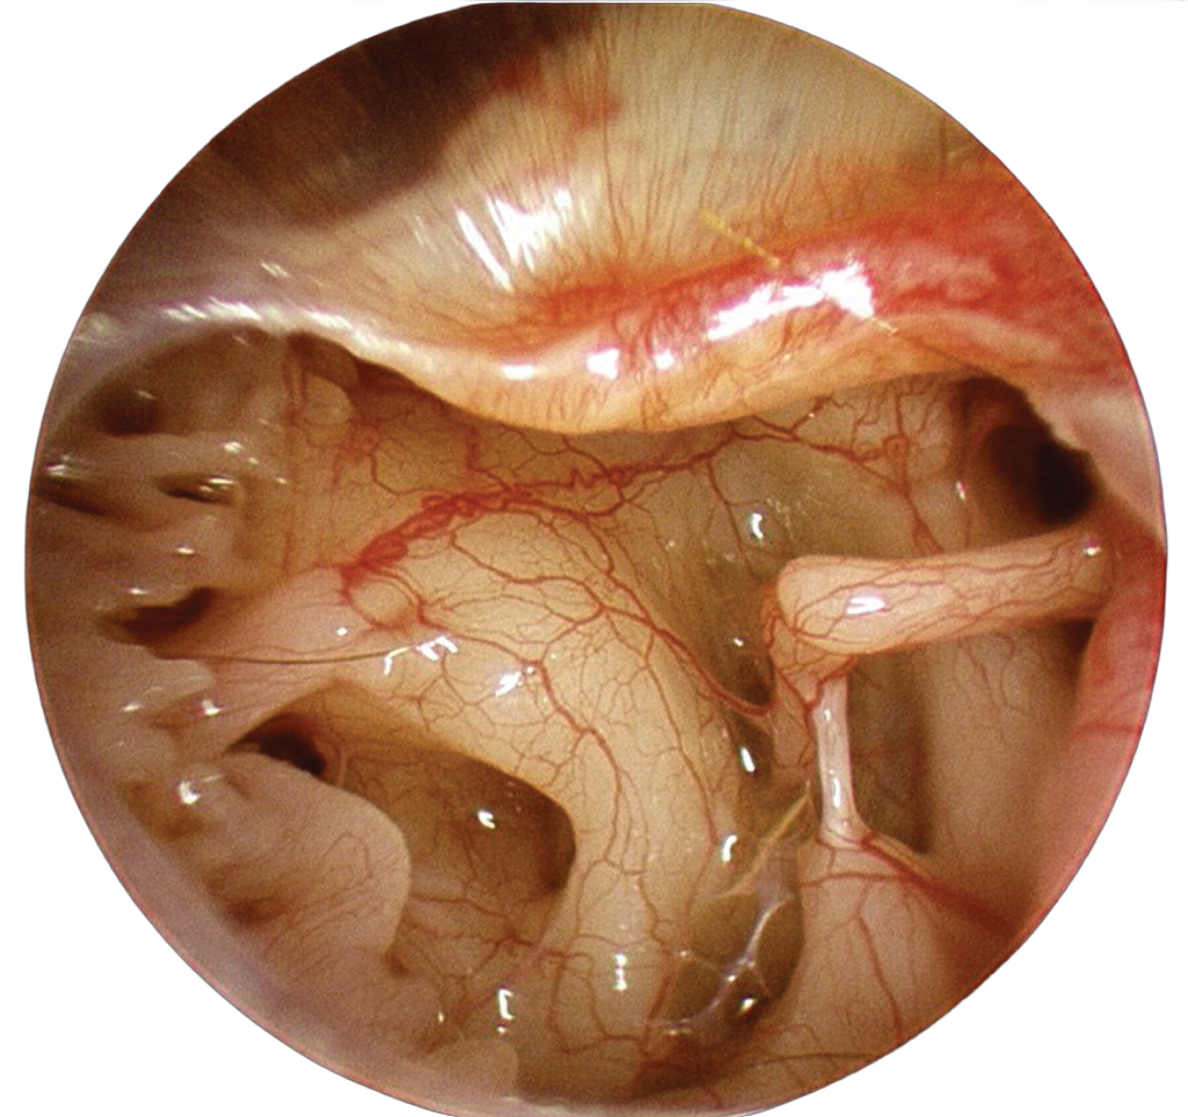

Prosidio's ApoClear™ Optic Technology utilizes premium apochromatic glass to deliver unparalleled clarity and precision. Experience exceptional optical quality and enhanced depth of field, crucial for detailed examination and surgical procedures.

The LuminEdge™ LED System provides brilliant, long-lasting illumination with a 50,000+ hour lifespan. Integrated green and yellow filters enhance visualization for specific procedures.